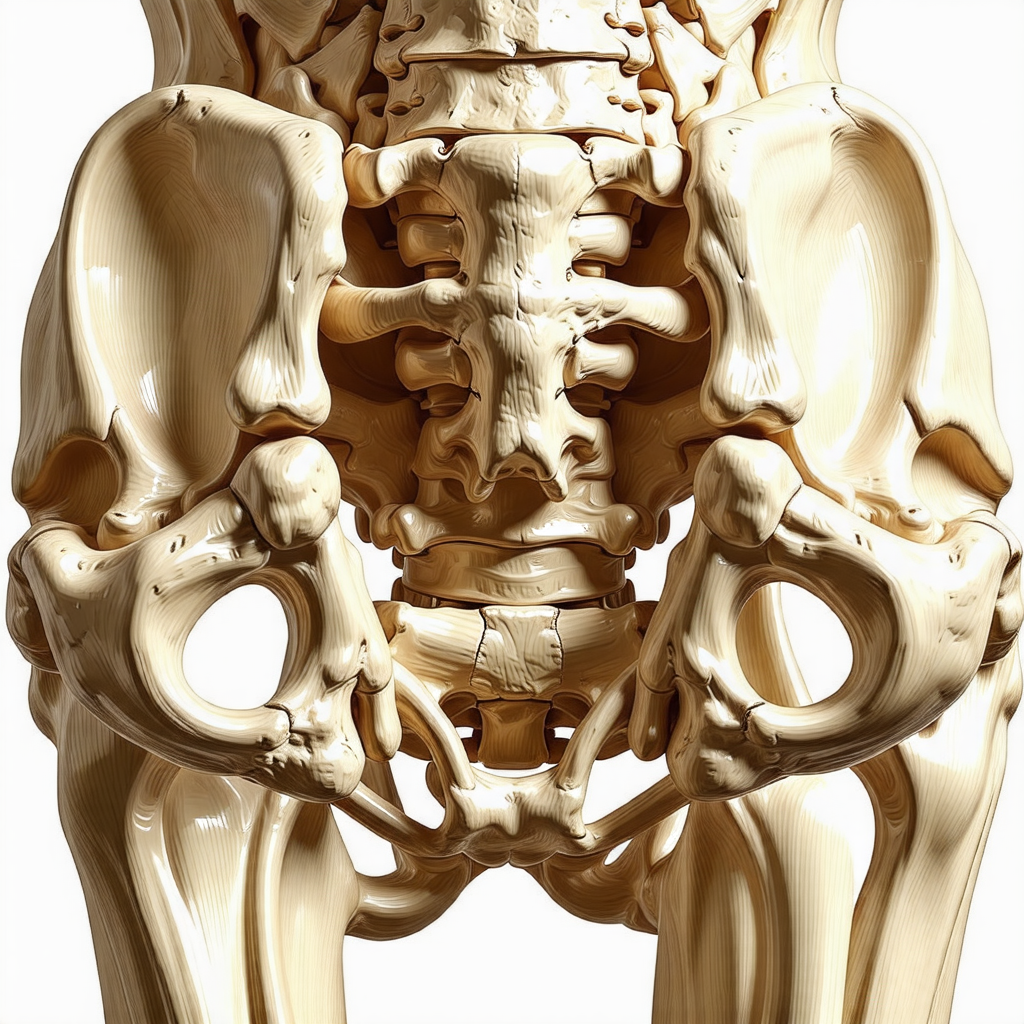

골다공증은 뼈의 밀도가 감소하여 뼈가 약해지고 쉽게 부러질 위험이 높아지는 질환입니다. 주로 노년층에게서 많이 발생하지만, 나이가 들기 전부터 예방에 신경을 쓴다면 건강한 뼈를 오래 유지할 수 있습니다. 골다공증을 예방하기 위해 알아야 할 중요한 정보와 방법을 자세히 살펴보겠습니다.

골다공증은 뼈 조직의 밀도가 감소하고 구조가 약해지는 질병입니다. 특히 여성의 경우 폐경 이후 에스트로겐의 감소로 인해 발병 위험이 높아지며, 남성보다 4배 이상 높은 발생률을 보입니다. 골다공증이 진행되면 일상생활 중 작은 충격에도 골절이 발생할 수 있으며, 이는 노년층의 건강을 심각하게 위협할 수 있습니다.